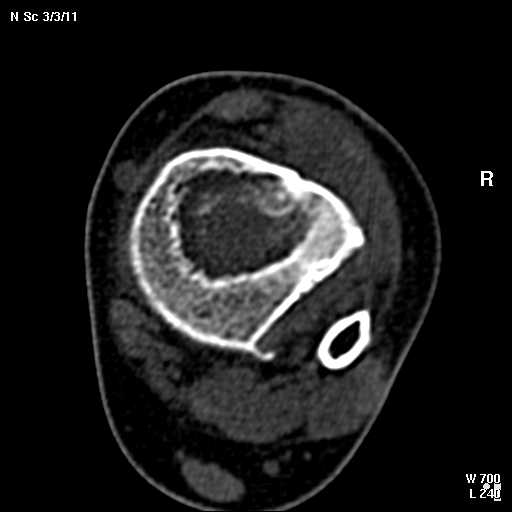

В обсуждении темы возникла необходимость дополнительных данных.

КТ изображения передаю на мой взгляд самые демонстративные. Их любезно записал коллега,

проводивший исследование в другом городе.

Прошу прощения за немного некоректную отправку КТ-снимков но по другому не получается :)